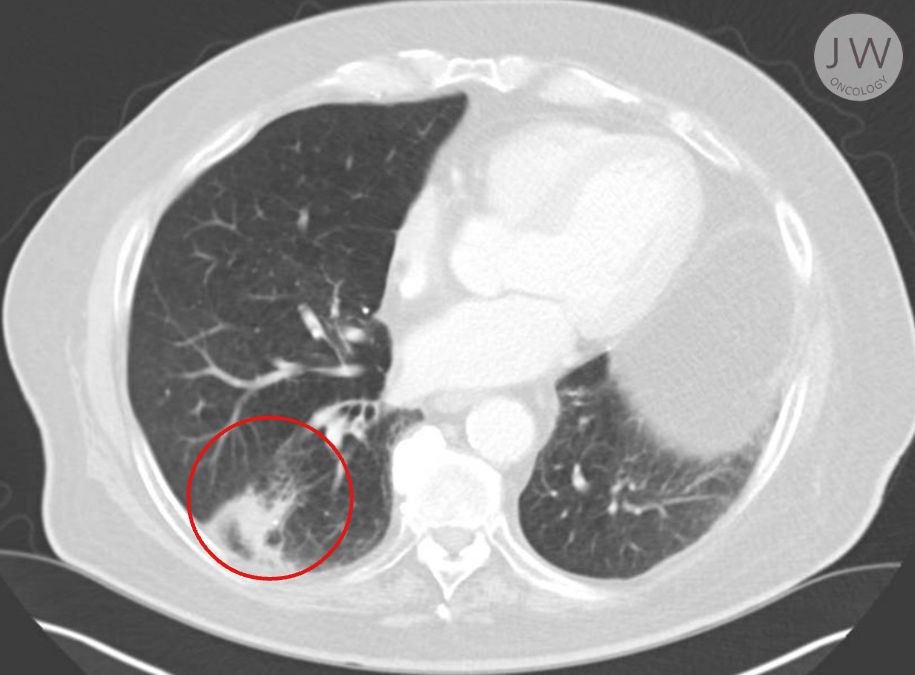

A particularly inspiring case of mine is that of an 84-year old man who had been diagnosed with early-stage lung cancer in the right lower lobe. Due to underlying heart conditions, surgery posed too great a risk, making him an ideal candidate for stereotactic ablative radiotherapy (SABR).

In the below photo, I’ve circled where the cancer was present in the patient. This was a tumour that, if left for a long period of time, could have caused significant damage to the patient’s lungs. Thankfully, early detection and a speedy treatment plan gave him a positive outcome.

Treatment Plan: Five short treatment sessions on alternate days

Side Effects: Mild fatigue but otherwise well tolerated

Outcome: One year after treatment, imaging showed no evidence of cancer, only fibrosis and scarring.